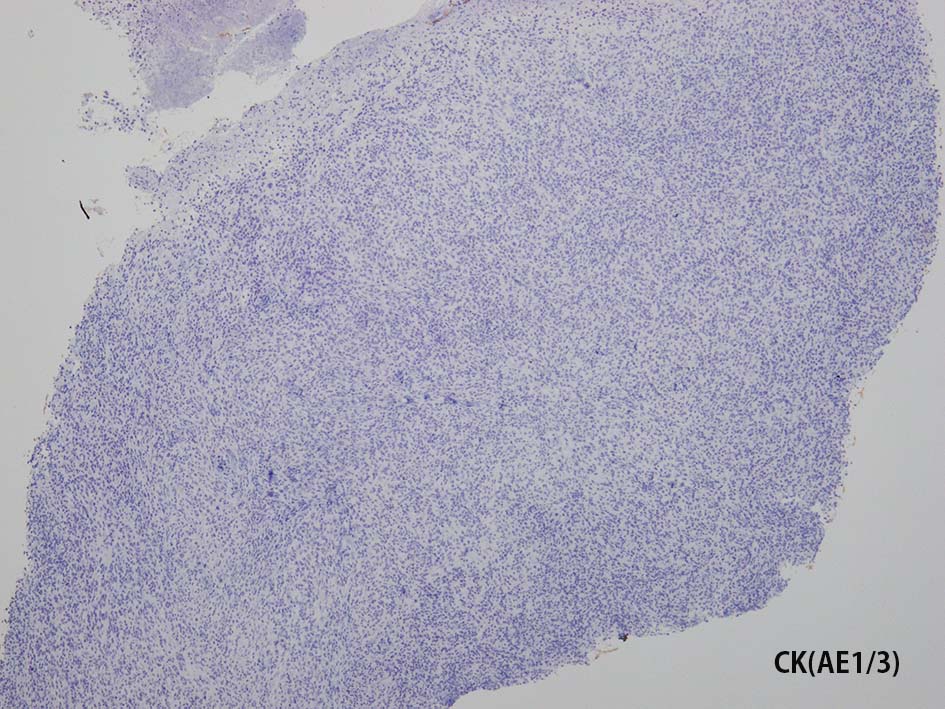

CD20, PAX5, CD3, CD5 リンパ球マーカは陰性. Dendritic cell marker (CD1a, CD123, Langerin, etc)は陰性. S-100, CD168, CD68(KP-1)が陽性. 組織球増殖病変と考えられた. foamy macrophageやgiant cellsはほとんど認められない. 高異型度, 多型細胞の出現はないが, MIB-1 LIが高く, mitosisも増加している, 悪性の心配あり, 治療方針の決定のため consultationを行った.

IHCの拡大像. Factor XⅢaの免疫染色画像もここに掲載する.